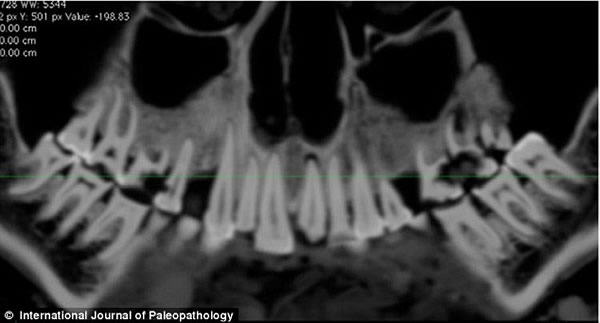

上图是木乃伊口腔CT扫描图,可以看到亚麻布团被填充在右部。

CT片显示了木乃伊左边第一颗门牙(左图)和右边第二颗门牙(右图)的磨损状况。

《古病理学国际期刊》的文章称,来自加拿大西安大略大学的安德鲁·韦德利用一种新型高分辨率CT仪扫描木乃伊的牙齿和身体,并且根据扫描片重建了3D图以进行更为细致的研究。从CT扫描片可以看到,木乃伊的一颗牙齿龋洞里塞着一块亚麻布团。这块亚麻布之前可能经过无花果汁液或雪松油等药物的浸泡,随后被塞入下颚第一、二颗臼齿中间,也就是最大、也是最疼的龋洞里。这么做既能起到抵挡食物残渣进入龋洞的屏障作用,又能利用亚麻布上的药物缓解疼痛。